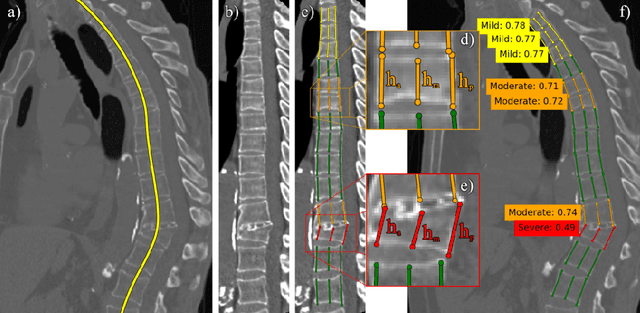

Abstract:Vertebral body compression fractures are early signs of osteoporosis. Though these fractures are visible on Computed Tomography (CT) images, they are frequently missed by radiologists in clinical settings. Prior research on automatic methods of vertebral fracture classification proves its reliable quality; however, existing methods provide hard-to-interpret outputs and sometimes fail to process cases with severe abnormalities such as highly pathological vertebrae or scoliosis. We propose a new two-step algorithm to localize the vertebral column in 3D CT images and then detect individual vertebrae and quantify fractures in 2D simultaneously. We train neural networks for both steps using a simple 6-keypoints based annotation scheme, which corresponds precisely to the current clinical recommendation. Our algorithm has no exclusion criteria, processes 3D CT in 2 seconds on a single GPU, and provides an interpretable and verifiable output. The method approaches expert-level performance and demonstrates state-of-the-art results in vertebrae 3D localization (the average error is 1 mm), vertebrae 2D detection (precision and recall are 0.99), and fracture identification (ROC AUC at the patient level is up to 0.96). Our anchor-free vertebra detection network shows excellent generalizability on a new domain by achieving ROC AUC 0.95, sensitivity 0.85, specificity 0.9 on a challenging VerSe dataset with many unseen vertebra types.

Abstract:Vertebral body compression fractures are reliable early signs of osteoporosis. Though these fractures are visible on Computed Tomography (CT) images, they are frequently missed by radiologists in clinical settings. Prior research on automatic methods of vertebral fracture classification proves its reliable quality; however, existing methods provide hard-to-interpret outputs and sometimes fail to process cases with severe abnormalities such as highly pathological vertebrae or scoliosis. We propose a new two-step algorithm to localize the vertebral column in 3D CT images and then to simultaneously detect individual vertebrae and quantify fractures in 2D. We train neural networks for both steps using a simple 6-keypoints based annotation scheme, which corresponds precisely to current medical recommendation. Our algorithm has no exclusion criteria, processes 3D CT in 2 seconds on a single GPU, and provides an intuitive and verifiable output. The method approaches expert-level performance and demonstrates state-of-the-art results in vertebrae 3D localization (the average error is 1 mm), vertebrae 2D detection (precision is 0.99, recall is 1), and fracture identification (ROC AUC at the patient level is 0.93).